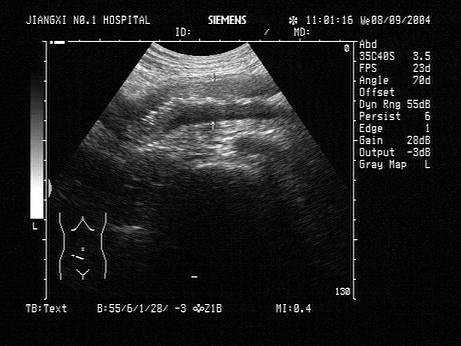

问题 患者,女,43岁,腹部不适,腹泻2周,体温37.9℃。右下腹部超声声像图表现如图,肠管蠕动不明显,最可能的诊断是?(?)

选项 A.克罗恩病 B.肠结核 C.肠梗阻 D.结肠癌 E.肠穿孔

答案 B